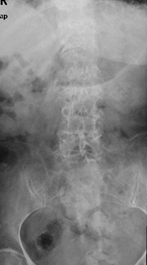

因:“腰椎骨折椎体成形术后2天”入院

患者因“脑卒中后遗症”在我中心康复治疗,于4月27日行走时滑倒腰部跌伤,当时即感疼痛,活动受限,到当地医院就诊,经CT等检查后,诊断为L3骨折,予卧床休息、口服活血化瘀及镇痛等对症治疗,患者自觉症状无改善,于6月03日在上级医院行椎体成形手术,2014年6月04日再次转入我中心继续康复治疗。患者入院时腰背部疼痛明显改善,并可下床活动。

神清,精神可,轮椅推入病房,精神略显紧张,发育正常,营养中等,呼吸平稳,查体合作,言语清晰,对答切题。全身皮肤粘膜无黄染,无皮疹、无淤斑、淤点,毛发分布正常,皮温正常、皮肤弹性正常,无肝掌。浅表淋巴结未及肿大。头颅大小正常,无畸形,眼睑无水肿,结膜无充血,眼球正常,无运动障碍,巩膜无黄染,角膜正常,双侧瞳孔等大等圆7.5px,对光反射正常。左侧鼻唇沟浅,左侧口角下垂,左侧额纹消失,耳廓正常,外耳道无脓性分泌物,乳突无压痛,双侧听力正常。鼻外形正常,鼻道畅,鼻中隔无偏曲,鼻旁窦无压痛。口唇红润无绀,口腔粘膜正常,舌正常,伸舌居中,牙龈无肿胀出血,咽无充血,双侧扁桃体未见肿大,声音正常。颈软,无抵抗,脑膜刺激征阴性,气管居中,颈静脉无充盈,双侧甲状腺未及肿大,无压痛。胸廓无明显畸形,乳头对称,双侧呼吸运动对称,语颤相等,叩诊清音,双肺呼吸音粗,未及明显干湿啰音。心前区未见异常隆起,心尖搏动位于左第5肋锁骨中线内12.5px,未及震颤,心相对浊音界正常。心率80次/分,律齐,各瓣膜听诊区未闻及病理性杂音。未及水冲脉、股动脉枪击音。腹平,未见腹壁静脉曲张,未见肠型蠕动波,腹软,无压痛、反跳痛,肝脾肋下未及,肾未触及,全腹未触及包块,肝肾区无叩痛,移动性浊音阴性,肠鸣音正常,5次/分。脊柱胸腰段后凸畸形,活动度轻度受限,棘突无明显叩痛,双下肢无水肿。四肢肌力正常,关节无畸形。双下肢感觉正常。

入院诊断:(1)腰椎骨折术后